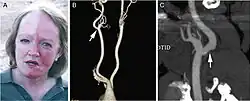

A man exhibiting the asymmetric symptoms of Harlequin syndrome. One half of the forehead is more red than the other.